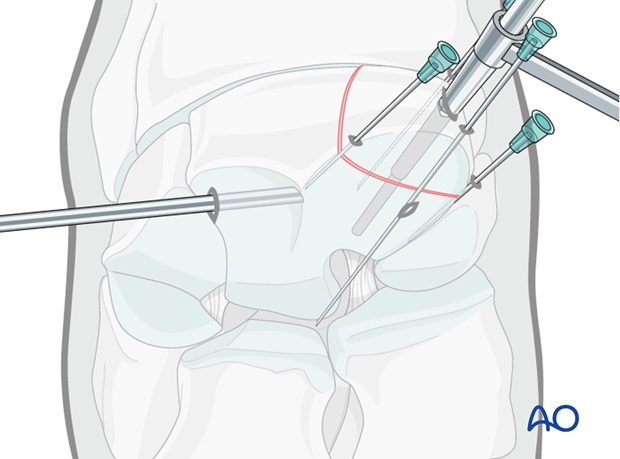

The 3.2 mm drill guide is inserted into the glide hole and the 3.2 mm thread hole is prepared through the remaining third carpal bone.

It is recommended that the hole is drilled completely through the entire bone to avoid the screw being longer than the hole which can result in screw breakage.

The hole is lightly countersunk at the dorsal surface and debris is flushed.

Correct screw length is determined using the depth gauge. The screw is generally 32-36 mm long.

The hole is tapped with a 4.5 mm tap protected by the 4.5 mm drill guide. This should be done by hand.